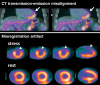

Positron emission tomography (PET) is increasingly being applied in the evaluation of myocardial perfusion. Cardiac PET can be performed with an increasing variety of cyclotron- and generator-produced radiotracers. Compared with single photon emission computed tomography, PET offers lower radiation exposure, fewer artifacts, improved spatial resolution, and, most important, improved diagnostic performance. With its capacity to quantify rest-peak stress left ventricular systolic function as well as coronary flow reserve, PET is superior to other methods for the detection of multivessel coronary artery disease and, potentially, for risk stratification. Coronary artery calcium scoring may be included for further risk stratification in patients with normal perfusion imaging findings. Furthermore, PET allows quantification of absolute myocardial perfusion, which also carries substantial prognostic value. Hybrid PET-computed tomography scanners allow functional evaluation of myocardial perfusion combined with anatomic characterization of the epicardial coronary arteries, thereby offering great potential for both diagnosis and management. Additional studies to further validate the prognostic value and cost effectiveness of PET are warranted.